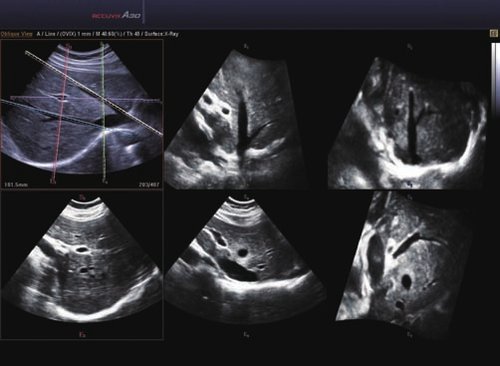

Das Samsung Accuvix A30 ist ein hochwertiges Ultraschallsystem, das mit seiner 3D-Technologie herausragende Ergebnisse ermöglicht. Das Sonographiegerät besitzt 5 Sondenanschlüsse und ist mit 20 unterschiedlichen Schallköpfen kompatibel. Mit dem A30 können Schallköpfe vom Typ Konvex, Mikrokonvex, 3D-Konvex, CW, Phased Array, Linear und Endokavitär verwendet werden. Bei zwei der Sonden handelt es sich um S-VUE Ultraschallsonden, die durch ihre höhere Bandbreite noch feinere Scans erzeugen.

Das Ultraschallsystem hebt sich besonders durch seine 3D-Technologie wie die Face Auto Detection für detaillierte Ultraschallbilder von Föten oder das Volume Shade Imaging, das sich auf die lebensnahe Darstellung von Schattierungen und Hauttönen fokussiert, ab. Mit weiteren wertvollen Technologien wie dem ElastoScan™ werden Tumore schneller erfasst und durch die HD Volumen Bildgebung sowie das DMR+™ eine erstklassige Bildqualität erzielt.

12 V2-6 3D Konvex 2-6 Abdomen, Frauenheilkunde und Geburtshilfe

13 V4-8 3D Konvex 4-8 Abdomen, Frauenheilkunde und Geburtshilfe

14 V5-9 3D Mikrokonvex 5-9 Abdomen

• 3D-Bildmodus

• 4D-Bildmodus.

• FAD™, die Face Auto Detection, stellt das Gesicht eines Fötus besonders detailliert dar. Überflüssige Daten werden entfernt und ein besonders realistisches Bild gezeichnet.

• Volume Shade Imaging, kurz VSI™, visualisiert ein 3D-Bild, das Hauttöne und Schattierungen auf ein qualitativ neues Niveau hebt.